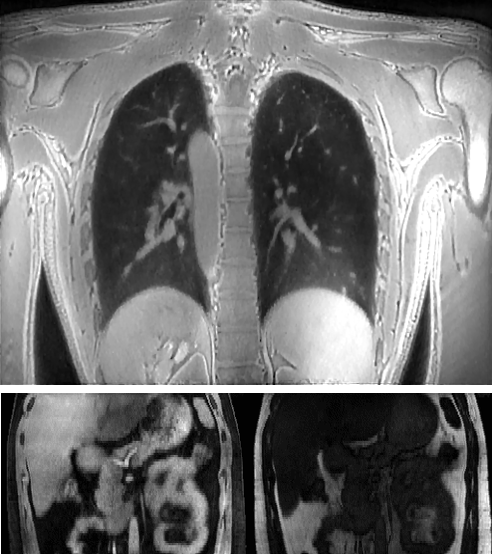

Medical imaging is now used extensively for accurate diagnosis, real-time intervention, and precision medicine. Our work has been focused on fast, high-resolution imaging augmented with functional and metabolic mapping. For example, dynamic 4D MRI under free breathing has been developed using PNCRNNs, with the reconstruction time as fast as 50 bin per second, offering substantial improvement of the image quality for dynamic golden-angle radial imaging of the abdomen. Novel imaging techniques have been developed for high-resolution whole-brain neurometabolic mapping, shedding light on in vivo molecular biomarkers for various brain diseases including stroke, brain tumor, and neurodegenerative disorders. A model-based deep learning architecture, referred to as MoDL-QSM, was developed with improved accuracy for quantifying tissue susceptibility for precise electrode implantation for deep-brain stimulation. To meet the demands for automated identification and localization of the vertebrae, pancreas, colon, lung nodules and other organs in low-dose CT, algorithms integrating local image details and global image patterns have been proposed. To extend the clinical use of nonlinear regression in medical imaging and image analysis, a deep negative correlation learning framework has been proposed to yield a deep regression of ensemble where each base model is both accurate and generalisable.

Dynamic 4D MRI of the abdomen

1.      Zhang Y, She H, and Du YP. Dynamic MRI of the abdomen using parallel non-cartesian convolutional recurrent neural networks. Magnetic Resonance in Medicine, 2021, 86:964-973.